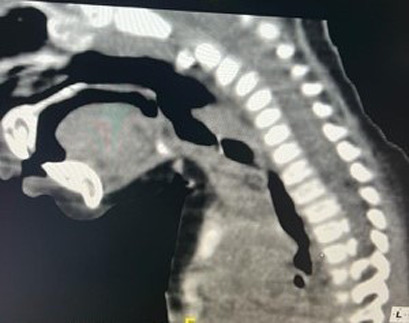

吸入异物在儿童中很常见,可能会危及生命。可以发现不同类型的异物,但喉部定位是罕见的。我们在此报告一例8个月大的男婴谁提出呼吸窘迫,发音困难,和喘。入院时,患儿表现出严重的喉部呼吸困难。颈椎CT扫描显示喉部有一不透射线的异物。内窥镜提取显示声门下有一阻生鱼椎体。位于下气道喉部的异物是罕见的,发现鱼椎骨是例外。

Inhalation of foreign bodies, a common occurrence in children, can be life-threatening. Different types of foreign bodies can be found, but laryngeal localization is rare. We here report the case of an 8-month-old male infant who presented with respiratory distress, dysphonia, and stridor. On admission, the child exhibited severe laryngeal dyspnea. Cervical CT scan revealed a radiopaque foreign body in the larynx. Endoscopic extraction revealed an impacted fish vertebra in the subglottis. Foreign bodies located in the laryngeal area of the lower airways are rare, and the discovery of a fish vertebra is exceptional.